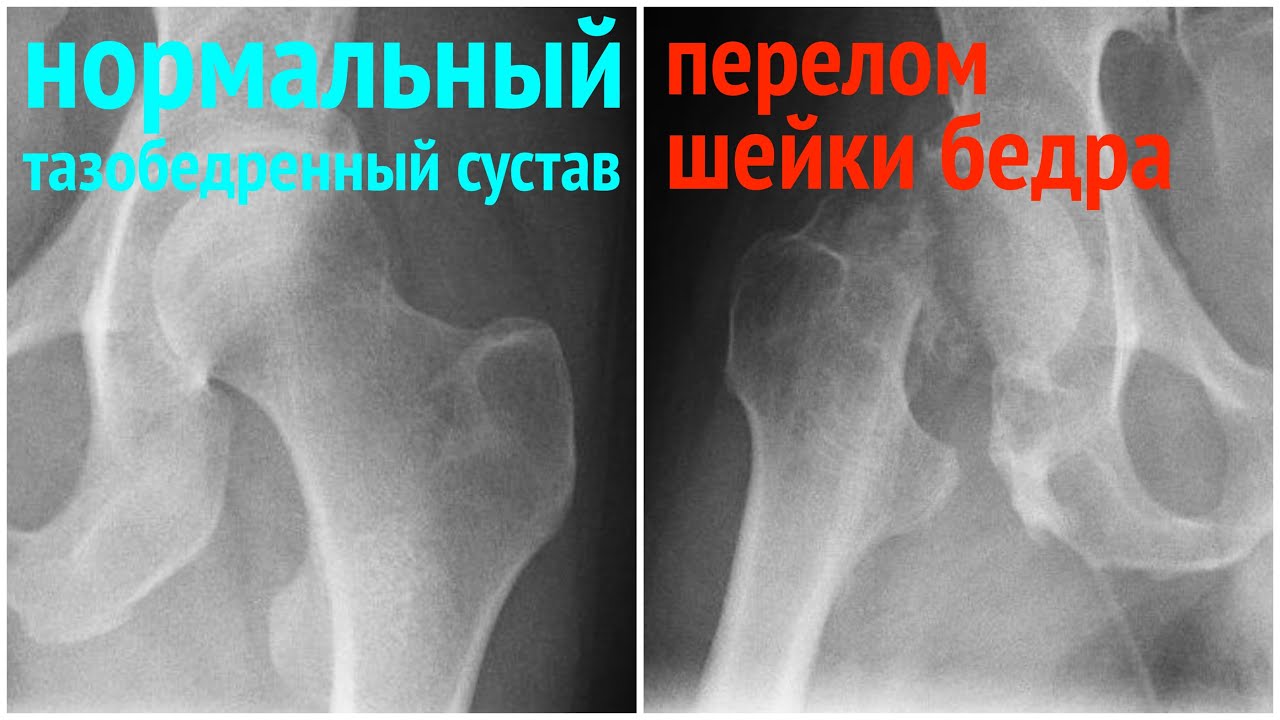

Шейка Бедра Фото Симптомы

Шейка Бедра Фото Симптомы 113 фотографий